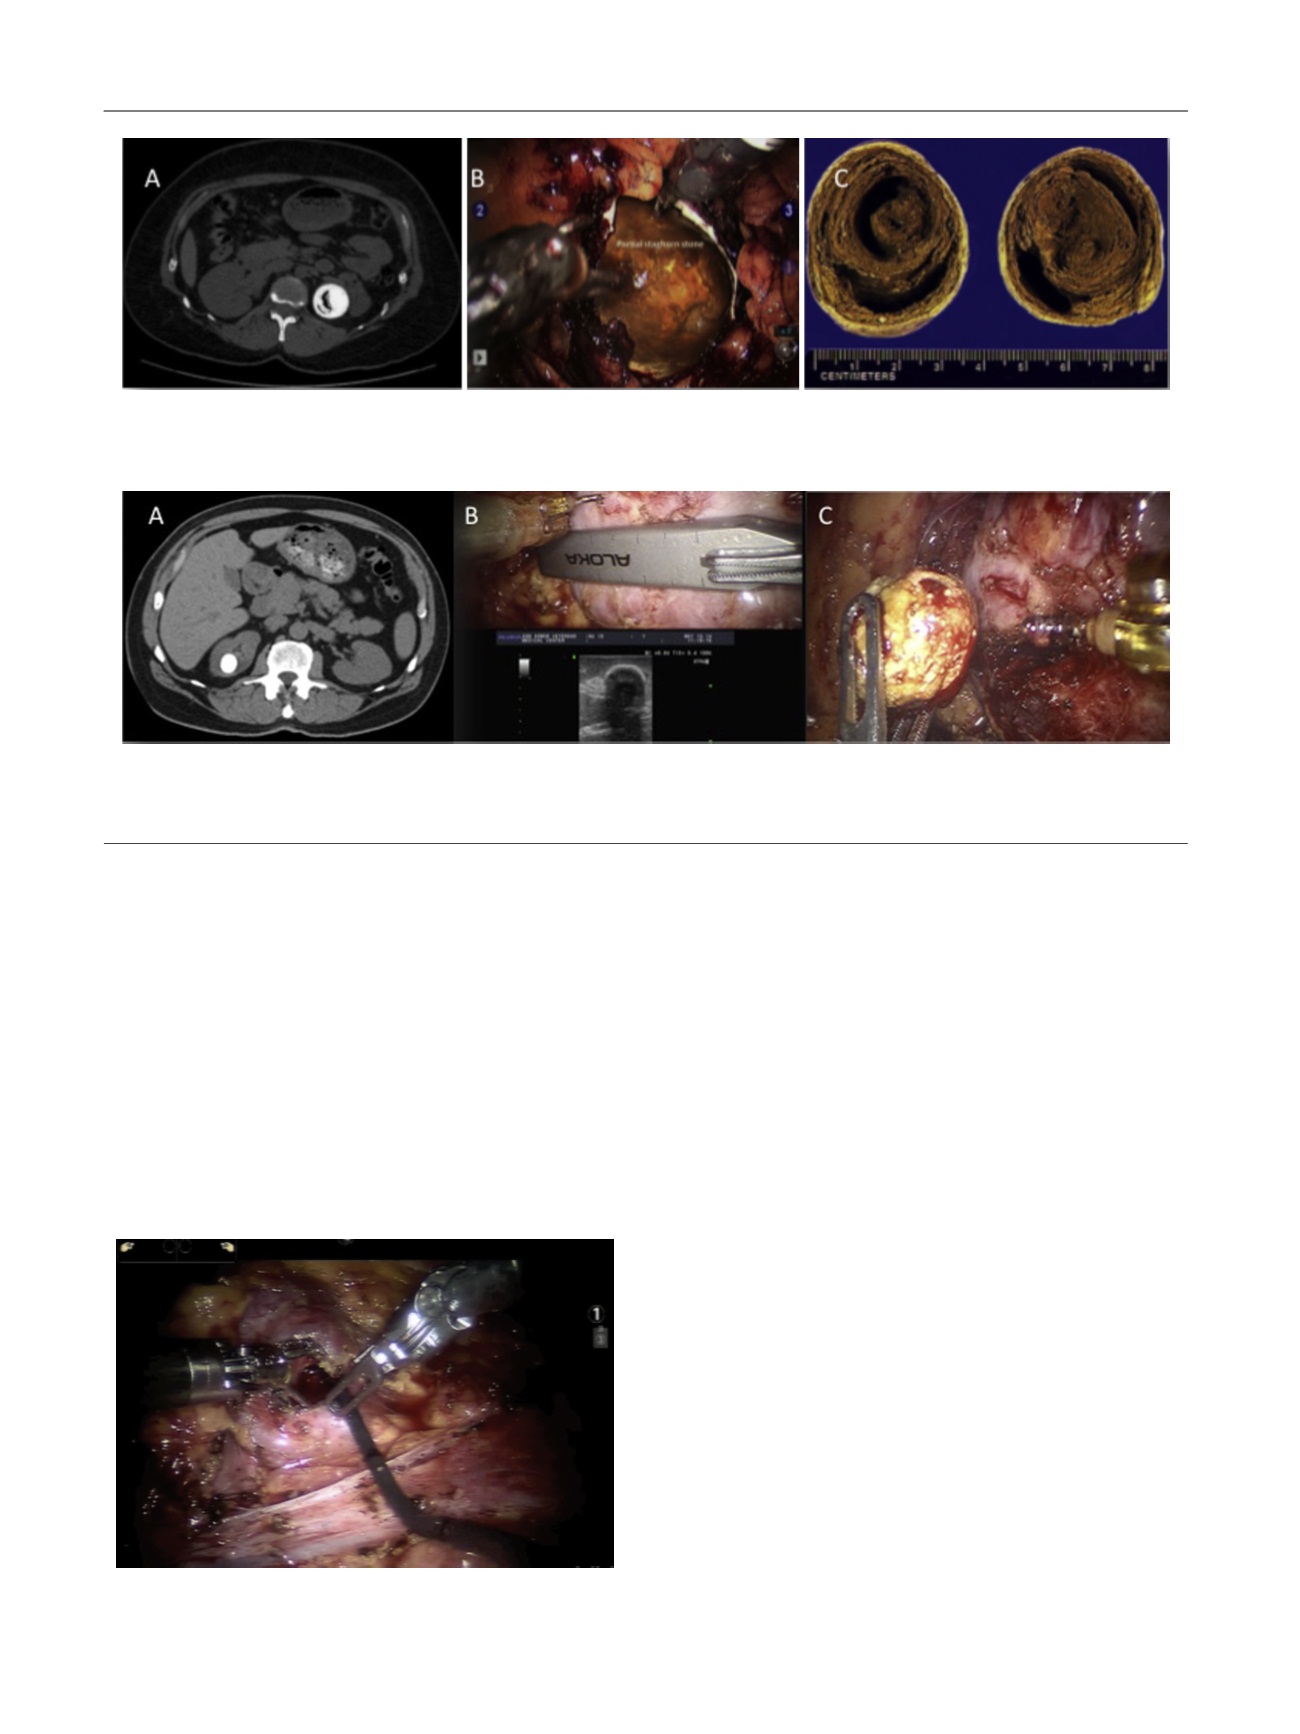

Fig. 1 – Robotic pyelolithotomy performed for a large pelvic stone. (A) Computed tomography scan demonstrating a 3.6-cm pelvic stone with possible

gas in the stone. (B) Pyelolithotomy incision exposing the stone. (C) Sectioned large left gas-containing renal stone.

[(Fig._2)TD$FIG]

Fig. 2 – Robotic nephrolithotomy performed for an upper pole stone. (A) A 2-cm upper stone within a diverticulum noted on computed tomography

scan. (B) A robotic ultrasound probe is utilized to identify and confirm the location of the stone and plan the incision. (C) A robotic ProGrasp forcep is

then used to carefully extract and remove the stone in its entirety.